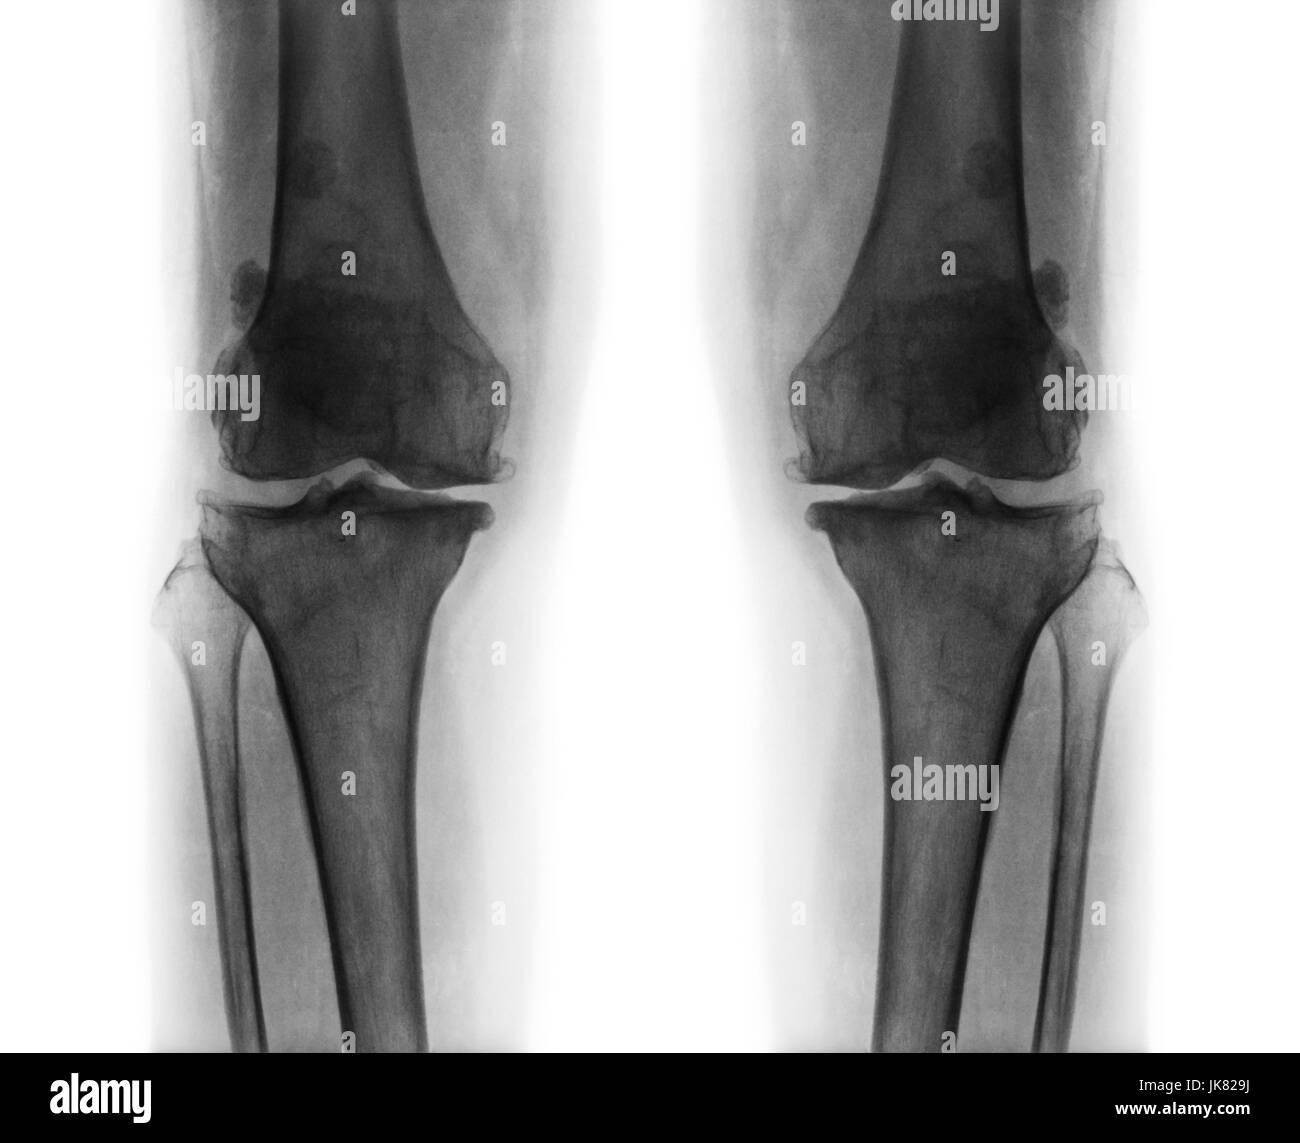

Flim X-ray genou AP : montrer l'articulation du genou humain normal Banque D'Imageshttps://www.alamyimages.fr/image-license-details/?v=1https://www.alamyimages.fr/photo-image-flim-x-ray-genou-ap-montrer-l-articulation-du-genou-humain-normal-77253242.html

Flim X-ray genou AP : montrer l'articulation du genou humain normal Banque D'Imageshttps://www.alamyimages.fr/image-license-details/?v=1https://www.alamyimages.fr/photo-image-flim-x-ray-genou-ap-montrer-l-articulation-du-genou-humain-normal-77253242.htmlRFEDK58A–Flim X-ray genou AP : montrer l'articulation du genou humain normal

L'arthrose du genou les . film x-ray ( AP ) postérieure antérieure - de montrer l'espace commun du genou étroit éperon ( ostéophyte . ) . subcondral la sclérose en plaques . Banque D'Imageshttps://www.alamyimages.fr/image-license-details/?v=1https://www.alamyimages.fr/photo-image-l-arthrose-du-genou-les-film-x-ray-ap-posterieure-anterieure-de-montrer-l-espace-commun-du-genou-etroit-eperon-osteophyte-subcondral-la-sclerose-en-plaques-149538858.html

L'arthrose du genou les . film x-ray ( AP ) postérieure antérieure - de montrer l'espace commun du genou étroit éperon ( ostéophyte . ) . subcondral la sclérose en plaques . Banque D'Imageshttps://www.alamyimages.fr/image-license-details/?v=1https://www.alamyimages.fr/photo-image-l-arthrose-du-genou-les-film-x-ray-ap-posterieure-anterieure-de-montrer-l-espace-commun-du-genou-etroit-eperon-osteophyte-subcondral-la-sclerose-en-plaques-149538858.htmlRFJK829E–L'arthrose du genou les . film x-ray ( AP ) postérieure antérieure - de montrer l'espace commun du genou étroit éperon ( ostéophyte . ) . subcondral la sclérose en plaques .

L'arthrose du genou les . film x-ray ( AP ) postérieure antérieure - de montrer l'espace commun du genou étroit éperon ( ostéophyte . ) . subcondral la sclérose en plaques . Banque D'Imageshttps://www.alamyimages.fr/image-license-details/?v=1https://www.alamyimages.fr/photo-image-l-arthrose-du-genou-les-film-x-ray-ap-posterieure-anterieure-de-montrer-l-espace-commun-du-genou-etroit-eperon-osteophyte-subcondral-la-sclerose-en-plaques-149538864.html

L'arthrose du genou les . film x-ray ( AP ) postérieure antérieure - de montrer l'espace commun du genou étroit éperon ( ostéophyte . ) . subcondral la sclérose en plaques . Banque D'Imageshttps://www.alamyimages.fr/image-license-details/?v=1https://www.alamyimages.fr/photo-image-l-arthrose-du-genou-les-film-x-ray-ap-posterieure-anterieure-de-montrer-l-espace-commun-du-genou-etroit-eperon-osteophyte-subcondral-la-sclerose-en-plaques-149538864.htmlRFJK829M–L'arthrose du genou les . film x-ray ( AP ) postérieure antérieure - de montrer l'espace commun du genou étroit éperon ( ostéophyte . ) . subcondral la sclérose en plaques .

L'arthrose du genou les . film x-ray ( AP ) postérieure antérieure - de montrer l'espace commun du genou étroit éperon ( ostéophyte . ) . subcondral la sclérose en plaques . Banque D'Imageshttps://www.alamyimages.fr/image-license-details/?v=1https://www.alamyimages.fr/photo-image-l-arthrose-du-genou-les-film-x-ray-ap-posterieure-anterieure-de-montrer-l-espace-commun-du-genou-etroit-eperon-osteophyte-subcondral-la-sclerose-en-plaques-149538862.html

L'arthrose du genou les . film x-ray ( AP ) postérieure antérieure - de montrer l'espace commun du genou étroit éperon ( ostéophyte . ) . subcondral la sclérose en plaques . Banque D'Imageshttps://www.alamyimages.fr/image-license-details/?v=1https://www.alamyimages.fr/photo-image-l-arthrose-du-genou-les-film-x-ray-ap-posterieure-anterieure-de-montrer-l-espace-commun-du-genou-etroit-eperon-osteophyte-subcondral-la-sclerose-en-plaques-149538862.htmlRFJK829J–L'arthrose du genou les . film x-ray ( AP ) postérieure antérieure - de montrer l'espace commun du genou étroit éperon ( ostéophyte . ) . subcondral la sclérose en plaques .

L'arthrose du genou les . film x-ray ( AP ) postérieure antérieure - de montrer l'espace commun du genou étroit éperon ( ostéophyte . ) . subcondral la sclérose en plaques . Banque D'Imageshttps://www.alamyimages.fr/image-license-details/?v=1https://www.alamyimages.fr/photo-image-l-arthrose-du-genou-les-film-x-ray-ap-posterieure-anterieure-de-montrer-l-espace-commun-du-genou-etroit-eperon-osteophyte-subcondral-la-sclerose-en-plaques-149538859.html

L'arthrose du genou les . film x-ray ( AP ) postérieure antérieure - de montrer l'espace commun du genou étroit éperon ( ostéophyte . ) . subcondral la sclérose en plaques . Banque D'Imageshttps://www.alamyimages.fr/image-license-details/?v=1https://www.alamyimages.fr/photo-image-l-arthrose-du-genou-les-film-x-ray-ap-posterieure-anterieure-de-montrer-l-espace-commun-du-genou-etroit-eperon-osteophyte-subcondral-la-sclerose-en-plaques-149538859.htmlRFJK829F–L'arthrose du genou les . film x-ray ( AP ) postérieure antérieure - de montrer l'espace commun du genou étroit éperon ( ostéophyte . ) . subcondral la sclérose en plaques .